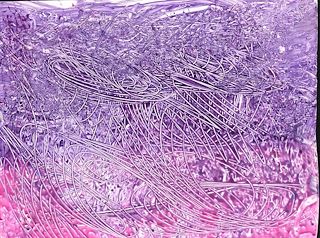

Artwork from Sadie9068

Art #136726360